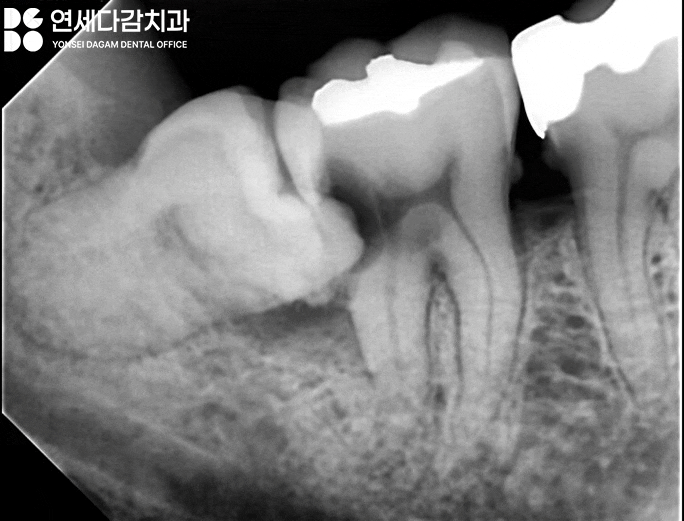

개롱역 치과 에서 보여드리는

사진을 보면 알 수 있듯이

하악 우측 사랑니(#48)가

제2대구치(#47)를 향해 기울어져

잘못된 맹출 방향이 이루어지면,

치아 사이에 생긴 공간에

음식물이 쉽게 끼는 환경이 조성됩니다.

심지어 구강 안쪽에 위치하다 보니

칫솔이나 치실로 청소하기가

까다롭습니다.

이런 원인들로 음식물이 낀 채로

방치됐을 때

문제가 발생합니다.

음식물이 오래 머물게 되면

세균이 활발하게 증식하며

충치를 유발하기 때문입니다.

개롱역 치과 에서 보여드린 증례는

식편압입(음식물 끼임) 현상으로

제2 대구치에 상당히 깊고 넓은

충치가 진행되어

통증까지 유발된 상황이었습니다.